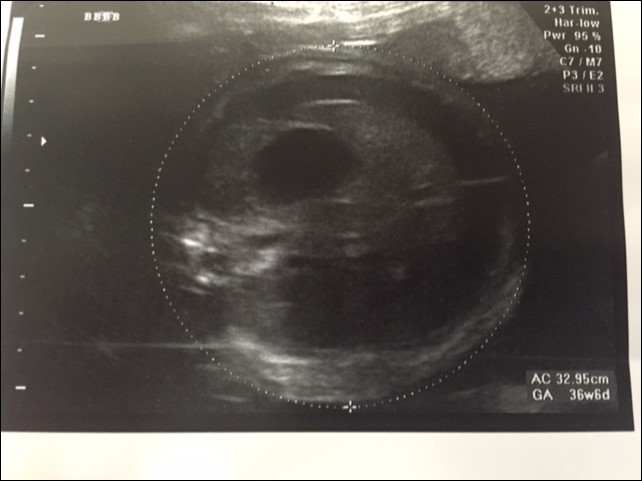

A 37 year old G3P2 female was referred to the pediatric surgical clinic for a twin pregnancy with one of the twins having a large left sided lung mass. The mother had a BMI of 48 and had undergone lap band surgery in the past. The lung mass was detected at 22nd week of gestation and was noted to be homogenous and solid on ultrasound and had a Cyst Volume Ratio (CVR) of 1.4. The twins were dichorionic diamniotic. Twin A had a posterior placenta and twin B (twin with the lung mass) had an anterior placenta. The lesion was located in the left hemi thorax and did not have any associated pleural effusion at first. The differential diagnosis for this lesion included a Stoker Type3 CPAM, a mediastinal teratoma, and a diaphragmatic hernia6. The Twin B was superior in the uterus in a breech position to the right side with a vertical pocket of amniotic fluid measurement of 6.8cm. The Bio Physical Profile score was 10/10. While the middle cerebral artery and ductus venosus dopplers were normal, there was some drop off in the end diastolic flow in the umbilical artery Dopplers. The mother was placed on weekly hi-definition ultrasound follow ups. Echocardiogram showed no structural cardiac defect. Steroids (betamethasone 12mg IM, two doses, 24hours apart) were administered after the development of pleural effusion was noted at the repeat ultrasound performed at 24 weeks and at this point CVR had increased to 1.6. As there was an inadequate response to steroid administration, with the development of a mediastinal shift from the mass effect of the lesion and significant pleural effusion, aspiration of the pleural fluid was performed twice (at weekly intervals during the 26th and 27th week of gestation) with recurrence of the effusion. The pleural fluid analysis showed that it was transudate on both occasions. The volume aspirated on each occasion was about 20 ml. Ascites was also detected and 10 ml of abdominal fluid was aspirated during the second aspiration. It appeared that the fetus was developing hydrops. During the 30th week ultrasound showed a significant mediastinal shift to the right, a large liver with ascites, and increased fetal skin thickness. A thoraco-amniotic shunt was placed at the 30th week of gestation and another course of steroids administered Figure 1 and Figure 2. The significant maternal subcutaneous fat would allow only a direct lateral access into the pleural cavity. The twin and mother were doing well with no symptoms. However, three weeks later, the fetus was able to dislodge the 'double-J' catheter and a second thoraco-amniotic shunt was placed because of recurrence of pleural effusion. While this was successful initially, the combination of the twin pregnancy and interventions led to premature delivery of the twins at 34 weeks gestation. MRI was not considered in the evaluation because of the large BMI.

Figure 1.Antenatal Ultrasound demonstrating the guide wire and shunt in position. The thickness of the amniotic fluid is being measured by the markers.